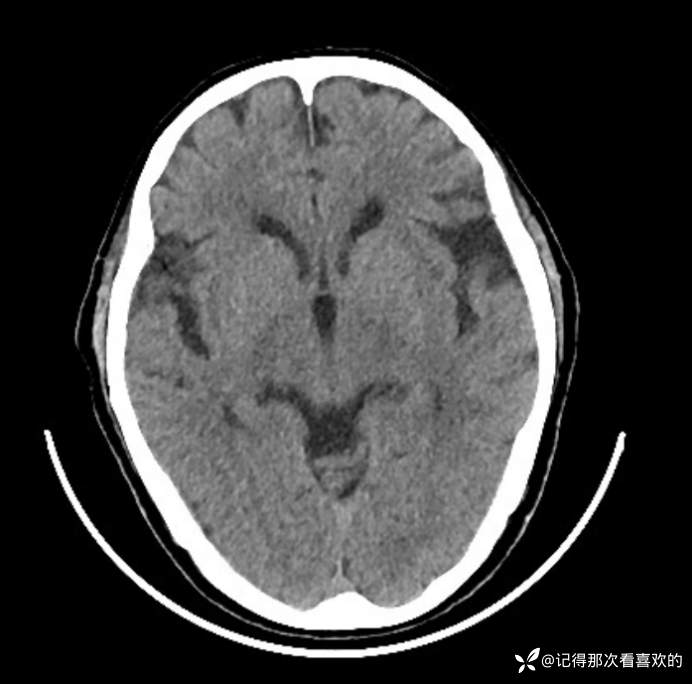

转科后查:2025-07-09血常规:*白细胞计数4.30×10^9/L,*血红蛋白120g/L,*血小板计数75×10^9/L↓;2025-07-11 铁蛋白 753.50ng/ml↑;血沉 12.00mm/h;降钙素原 0.21ng/ml,白介素6 329.0pg/mL↑;2025-07-12 血常规:*白细胞计数 4.99×10^9/L,中性粒细胞百分数78.9%↑,淋巴细胞计数 0.80×10^9/L↓,*血红蛋白115g/L,*血小板计数42×10^9/L↓;降钙素原1.21ng/ml,C反应蛋白35.50mg/L↑,白介素6 22.4pg/mL↑;血沉 14.00mm/h;甲型/乙型流感病毒抗原检测(呼吸道病毒抗原检测)、抗中性粒细胞胞浆抗体5项测定(ANCA)、登革热病毒检测(抗原+抗体)、新冠病毒核酸单人单检、粪便隐血试验(OB):阴性。免疫球蛋白G4(IgG4)、血液疟原虫检查、异常凝血酶原(PIVKA-Ⅱ)测定、粪便常规:未见明显异常。2025-07-11床边心电图:窦性心律,左心室高电压,ST-T异常。